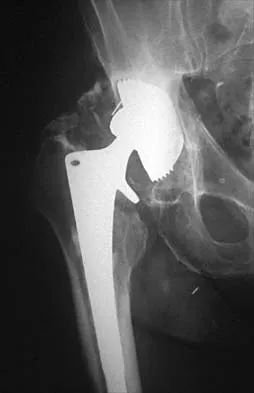

An otherwise healthy 57-year-old man has persistent, severe hip pain after undergoing total hip arthroplasty 3 months ago. What is the next most appropriate step in management?

Explanation